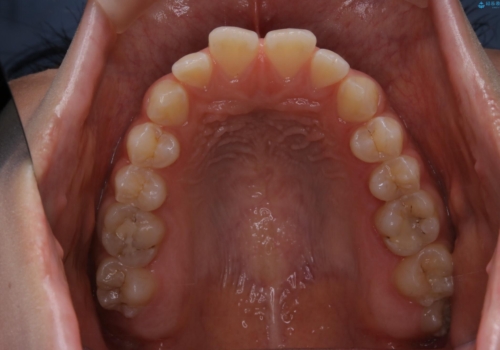

短期間ですきっ歯を改善:インビザラインLite

- 上の歯がすきっ歯なのと、歯が出ている気がするとご相談にいらした方です。

奥歯の噛み合わせに大きな問題がなく、患者様のご希望もあったため、前歯部メインで治療するインビザラインLiteで治療を行いました。

横顔のシルエットが改善し、口元もスッキリとなりました。